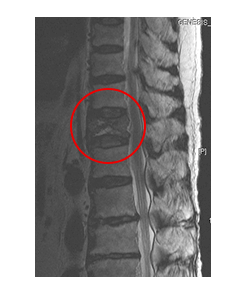

의사는 등과 허리검사와 진단을 위해 환자의 병력과 기저질환을 탐색하고, 이학적 검사와 신경학적 검진을 시행합니다. 단순 X-ray 촬영을 통해 간단하게 골절여부가 확인되지만 골절의 정도가 심하지 않거나, 다친 경험이 정확하지 않은 경우에는 정밀검사가 필요하기도 합니다.

또한, 신경손상등의 다른 심한 손상이 동반된 척추골절 분류에 포함되는지 확인하기 위해 허리검사 CT나 MRI 등의 정밀검사를 시행하기도 합니다. 급성 압박골절의 경우에는 허리 골절 수술을 시행하지 않더라도 MRI의 급여 적용이 가능합니다.